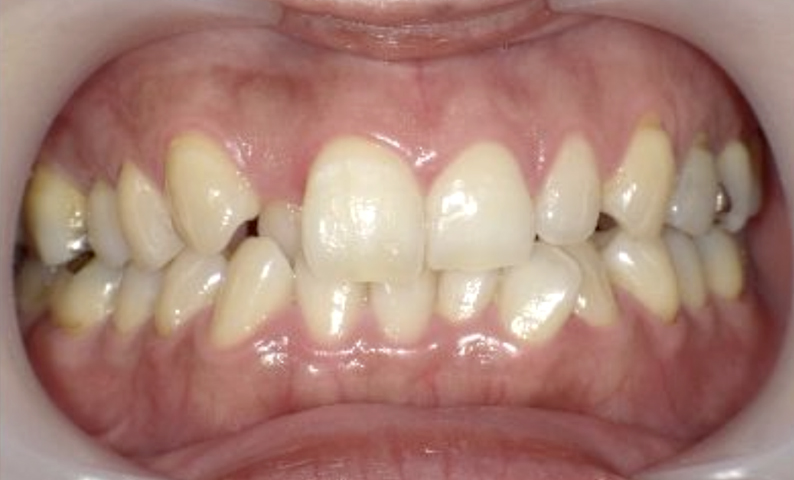

症例_029 上下顎の部分矯正

治療期間:12ヶ月金額:60万円+税女性出っ歯捻転歯前歯のガタガタ